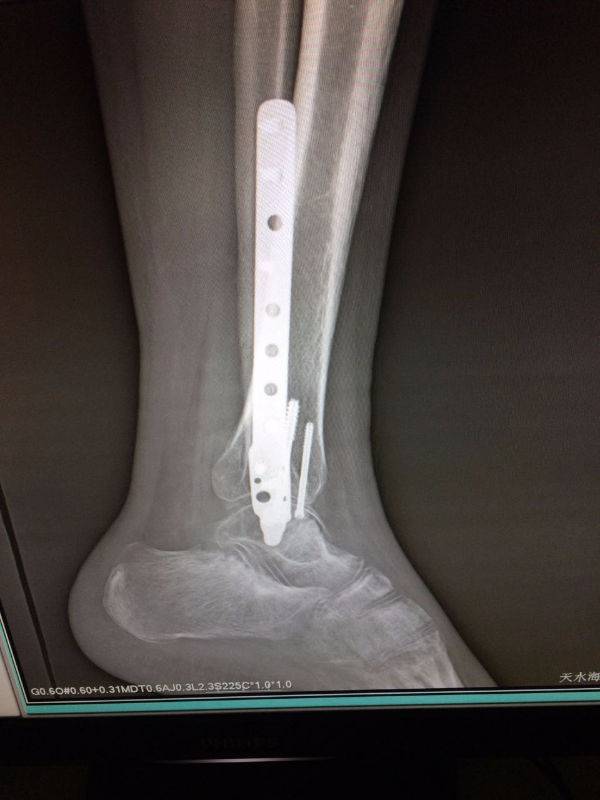

手术非常好,顺便请教一下。患者.男,25岁,右腓骨下段及内踝骨折,切开复位内固定术后120天,外踝部钢板外露,半月前行扩创缝合,目前仍未完全愈合,伴少量渗出,踝关节功能僵硬。请教治疗方案。谢谢

mmexport1496478281296.jpg

mmexport1496478334909.jpg

mmexport1496478329835.jpg

mmexport1496478319278.jpg